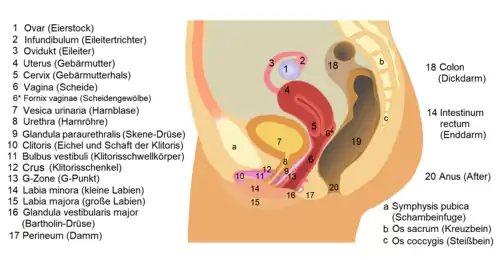

Untersuchung und Behandlung der weiblichen Geschlechtsorgane hingegen liegen in der Zuständigkeit der Gynäkologie und der Urogynäkologie. Naturgemäß ist die Zusammenarbeit mit Neurologen, Onkologen, Venerologen und Chirurgen nötig. Die Urologie steht „zum Teil in Konkurrenz mit der Nephrologie“,[2] diese ist ein Teilgebiet der Inneren Medizin. Zusätzlich bestehen Überschneidungen mit der Reproduktionsmedizin, der Dermatologie und der Endokrinologie.[3]